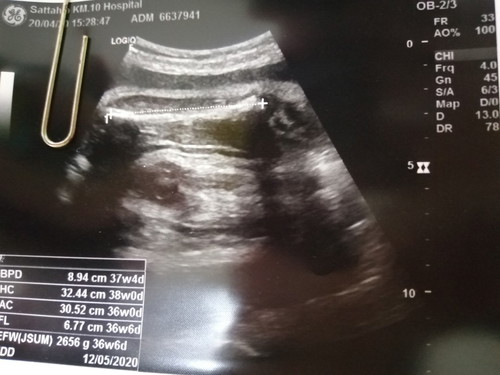

คุณแม่บ้านไหนลุ้นเพศลูกจนถึงตอนคลอดมั้ยคะ นี่ท้อง37สัปดาห์แล้วยังไม่รู้เพศลูกเลย?

เราก็ยังไม่รู้ค่ะ 55